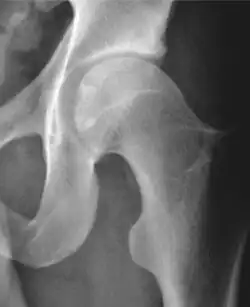

| Alpha angle | ![]() |

Degree of bulging of the femoral head-neck junction: In normal conditions there is a symmetric concave contour at the junction of the femoral head and neck. Loss of this concavity or bone bulging may lead to cam type impingement. The degree of this deformity can be measured by the alpha angle. Although it can be measured in the cross-lateral view, the 45° Dunn view is considered more sensitive and the frog leg view more specific in determining pathologic values. |

|